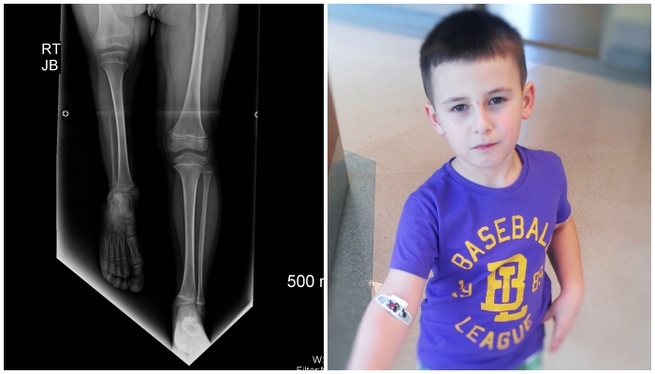

Chłopiec ma 11 lat. Urodził się z wrodzonym niedorozwojem kości udowej, jest po dwóch operacjach przeprowadzonych na Florydzie, przed nim kolejna - wydłużania kości udowej. Koszt operacji to około 560 tys. zł.

Prawe biodro chłopca nie wykształciło się prawidłowo, prawa noga jest znacznie krótsza od lewej. Amputacja – to słowo rodzice słyszeli od większości lekarzy. Jednak po 6 latach pojawiła się nadzieja. W Polsce, ani w Europie nie ma nikogo, kto mógłby pomóc Arturowi. W Stanach Zjednoczonych jest jednak lekarz, który jest stanie to zrobić.